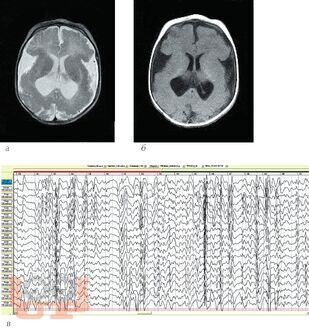

В учебном пособии рассматривается проблема диагностики и лечения резистентных форм эпилепсии у детей. Анализ материала основан на собственном опыте работы и данных литературы. В пособие включены редкие формы резистентных эпилептических энцефалопатий у детей. Особое внимание уделено нейрохирургическим методам лечения.